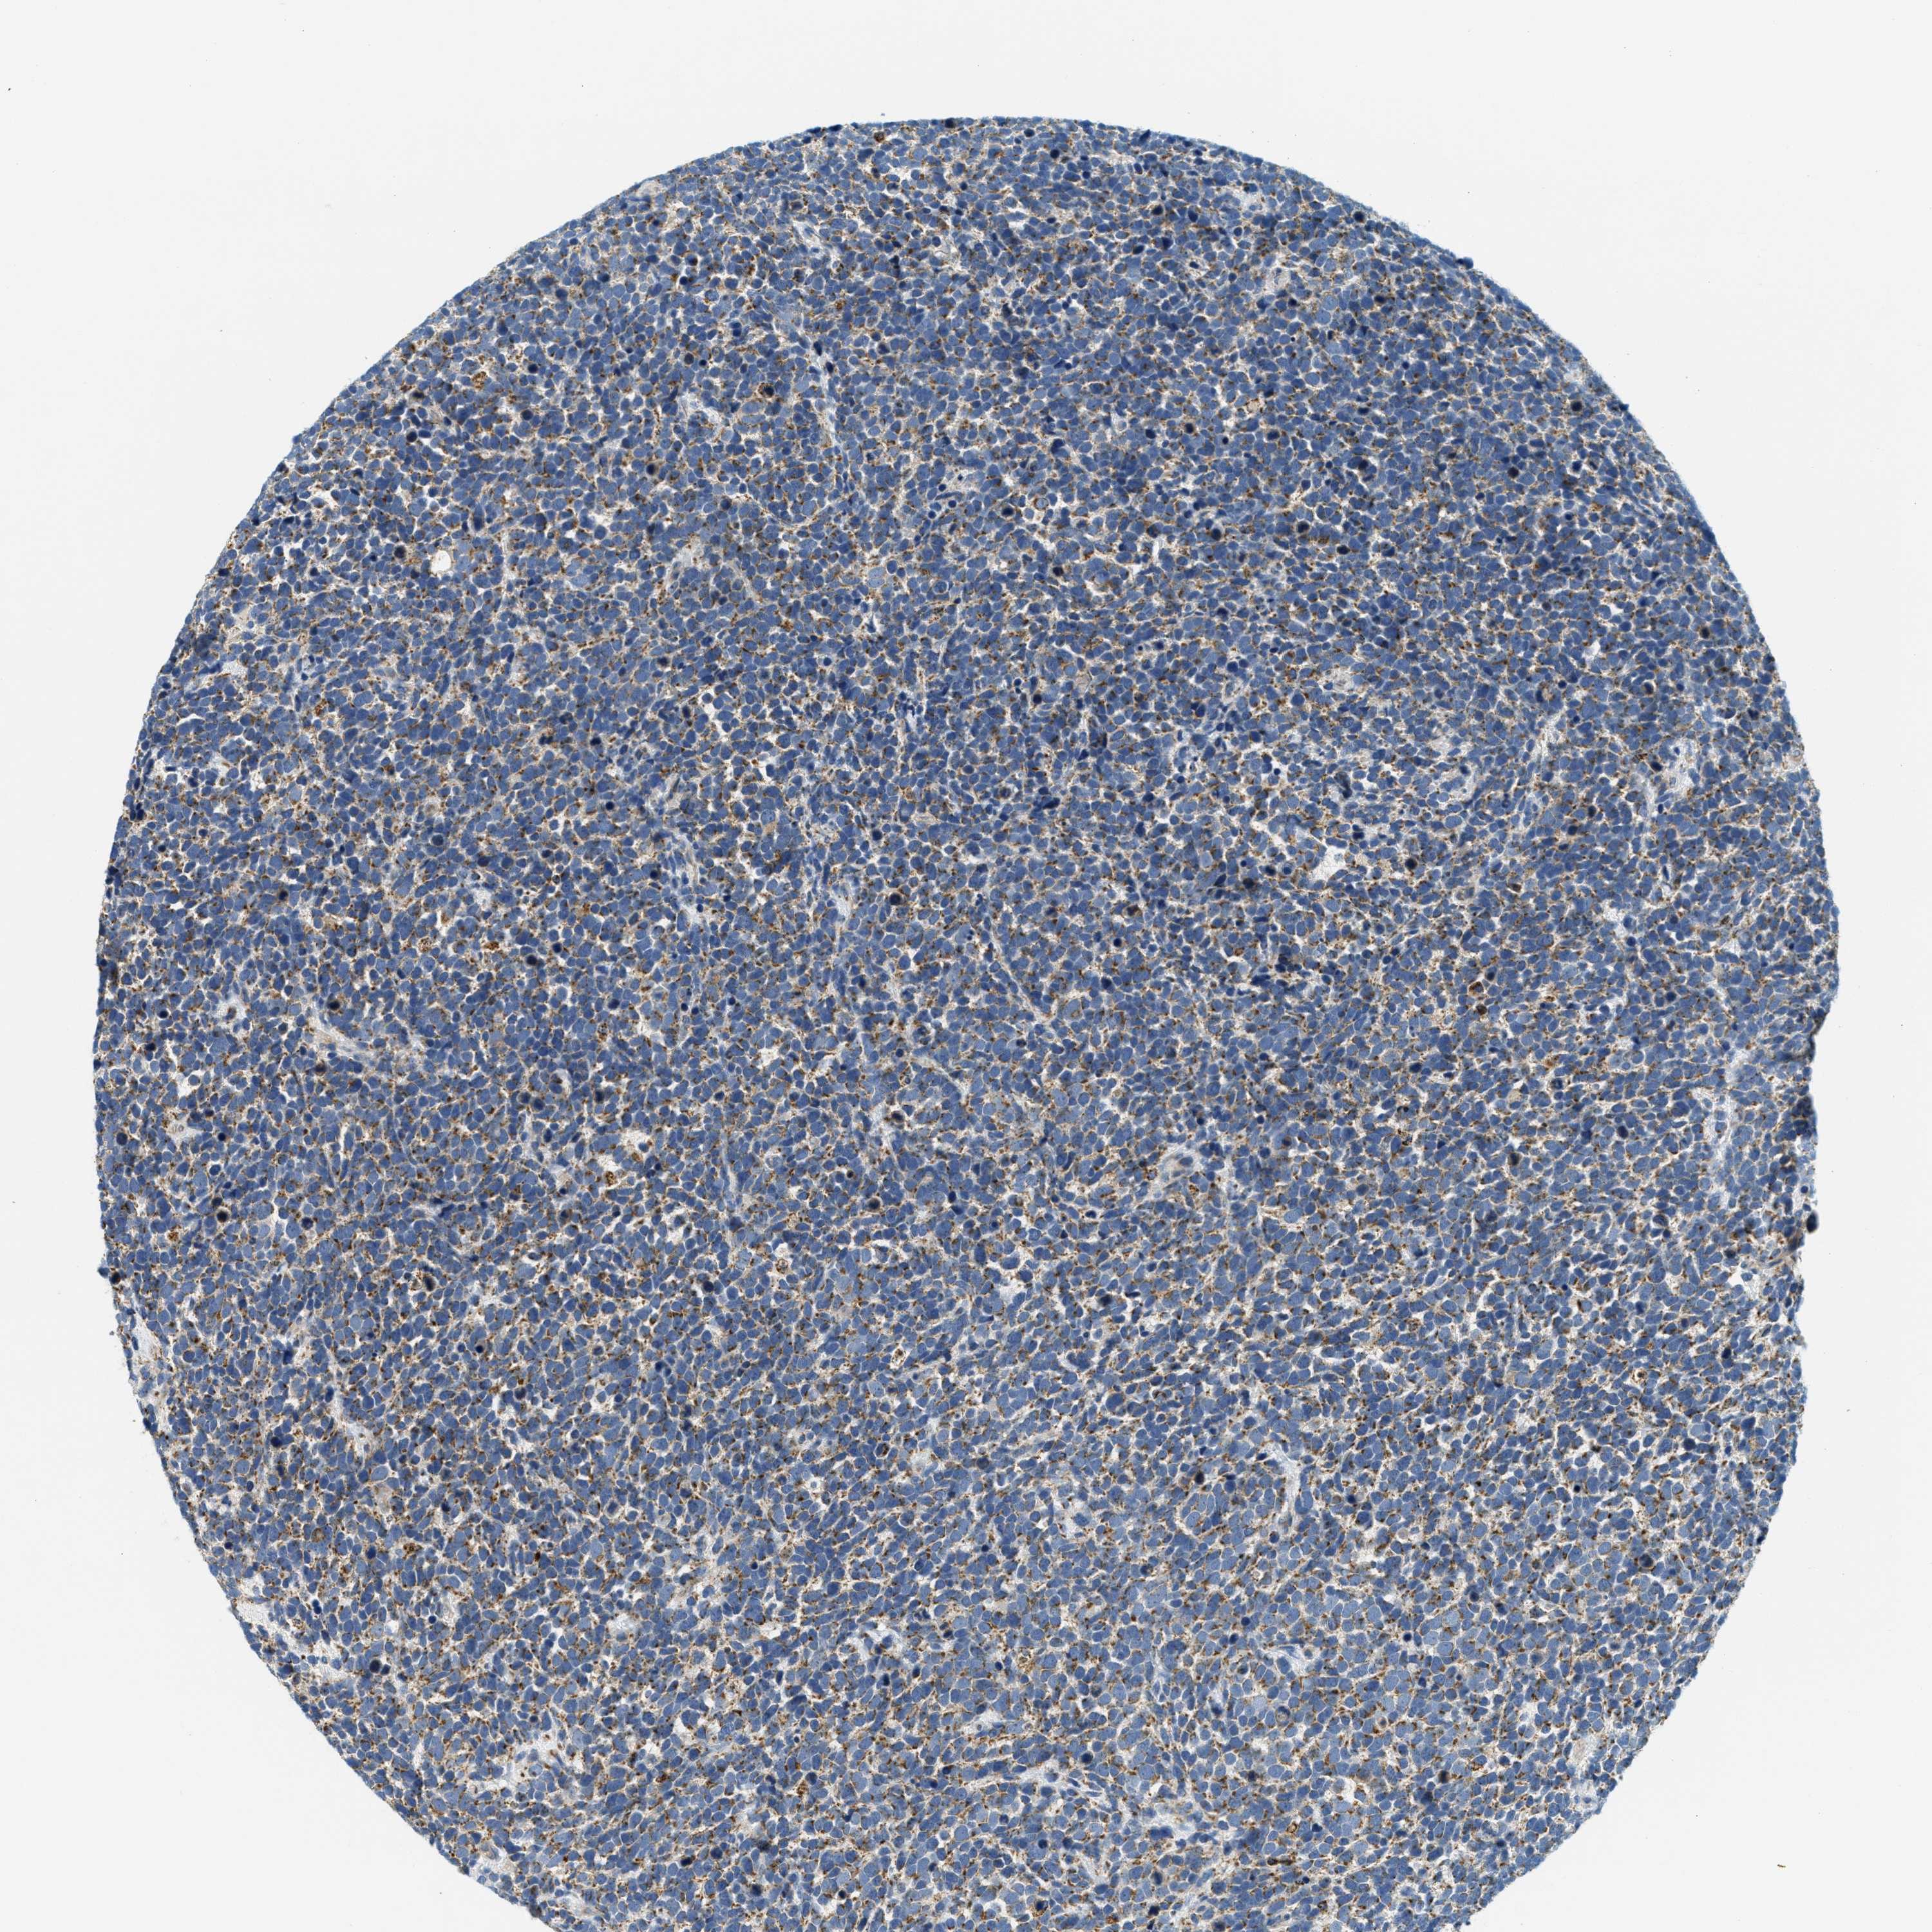

UROTHELIAL CANCER - Protein expressioni

A mouse-over function shows sample information and annotation data. Click on an image to view it in a full screen mode. Samples can be filtered based on level of antibody staining by selecting one or several of the following categories: high, medium, low and not detected. The assay and annotation is described here.

Note that samples used for immunohistochemistry by the Human Protein Atlas do not correspond to samples in the TCGA dataset.

Antibody stainingi

Antibody staining in the annotated cell types in the current human tissue is reported as not detected, low, medium, or high, based on conventional immunohistochemistry profiling in selected tissues. This score is based on the combination of the staining intensity and fraction of stained cells.

Each image is clickable and will lead to virtual microscopy that enables deeper exploration of all samples and also displays staining intensity scores, fraction scores and subcellular localization as well as patient and tissue information for each sample.

Antibody HPA017379

Staining

High

Medium

Low

Not detected

Intensity

Strong

Moderate

Weak

Negative

Quantity

>75%

75%-25%

<25%

None

Location

Nuclear

Cytoplasmic/membranous

Cytoplasmic/membranous,nuclear

Urothelial carcinoma, Low grade

Urothelial carcinoma, High grade